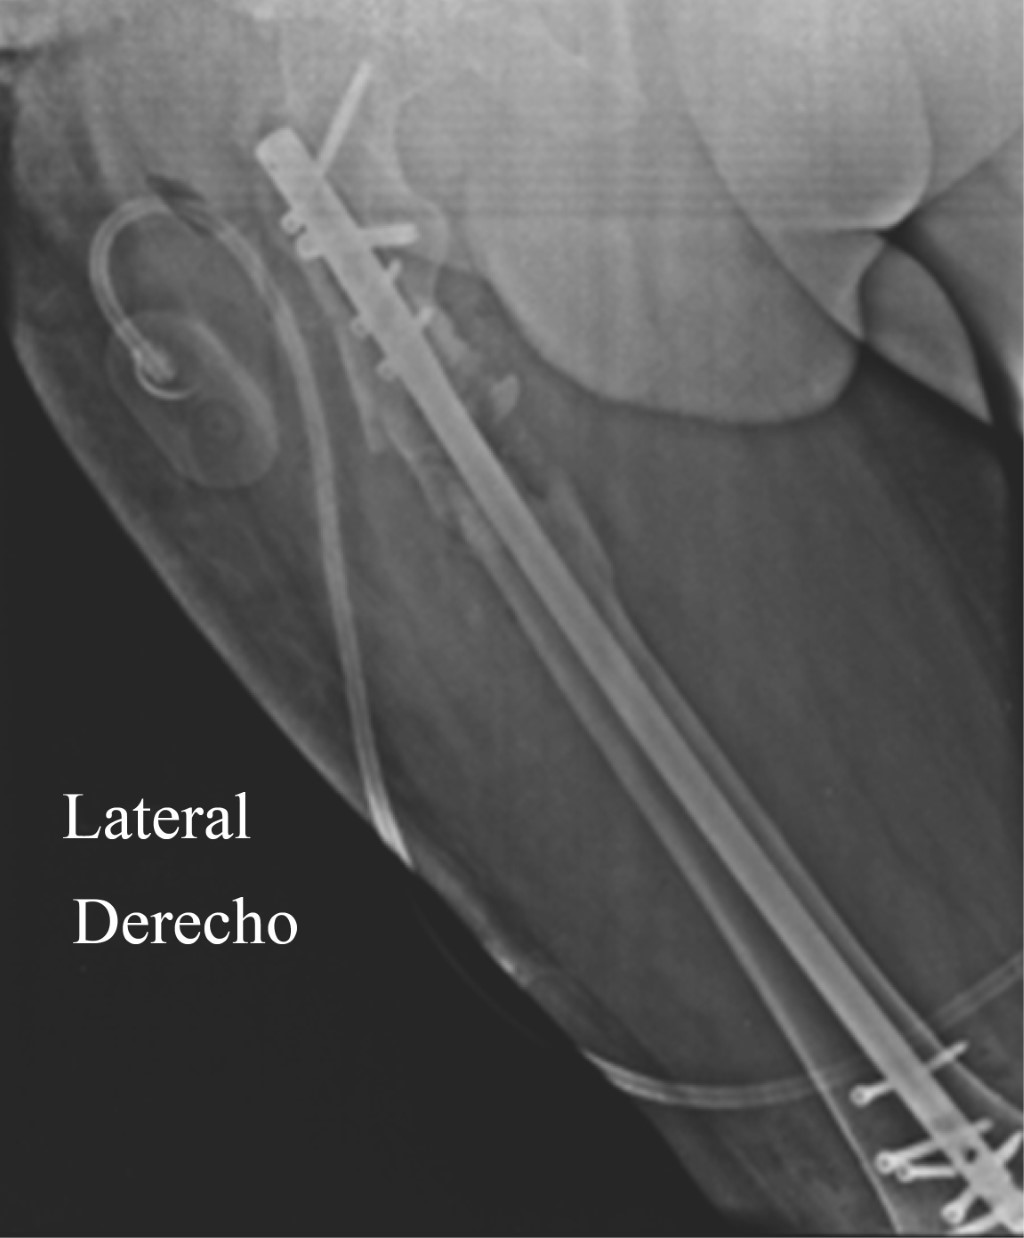

En Mayo de 2020 por persistencia de la infección se retira el material de osteosíntesis, se deja un clavo TENS endomedular recubierto de cemento con antibióticos (gentamicina) (Figura 5). A finales de Mayo después de dos lavados quirúrgicos se retiró el clavo TENS, resección de bordes de fractura (hasta hueso sano) injerto óseo endomedular con un segmento de 10 cm de peroné no vascularizado (autólogo) y fijación de la fractura con una placa de soporte condíleo de fémur distal (Figura 6); colocación de sistema VAC y cierre definitivo de la herida en un segundo tiempo el 28 de Mayo de 2020.

Figura 6